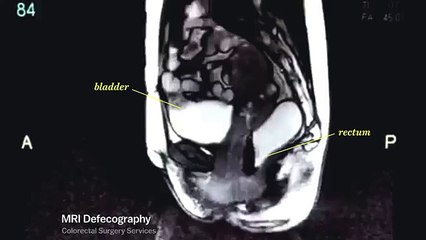

Life looks really different through an MRI machine